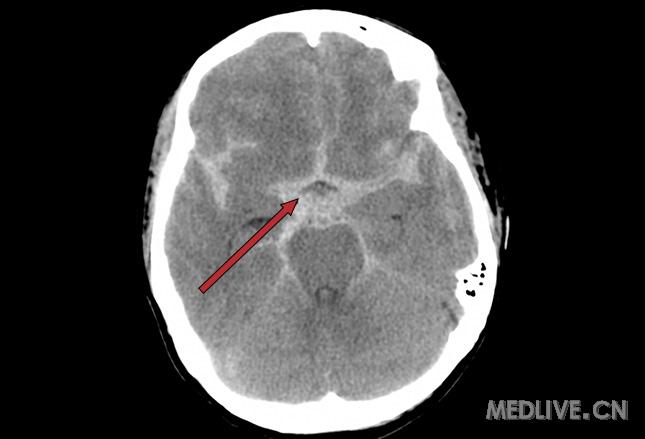

蛛网膜下腔出血ct图片

蛛网膜下腔出血ct图片,蛛网膜 结构图

入院时头颅ct影像可见广泛蛛网膜下腔出血.

图中的脑ct图像显示willis环内存在高密度影,符合蛛网膜下腔出血表现.

头部ct提示蛛网膜下腔出血